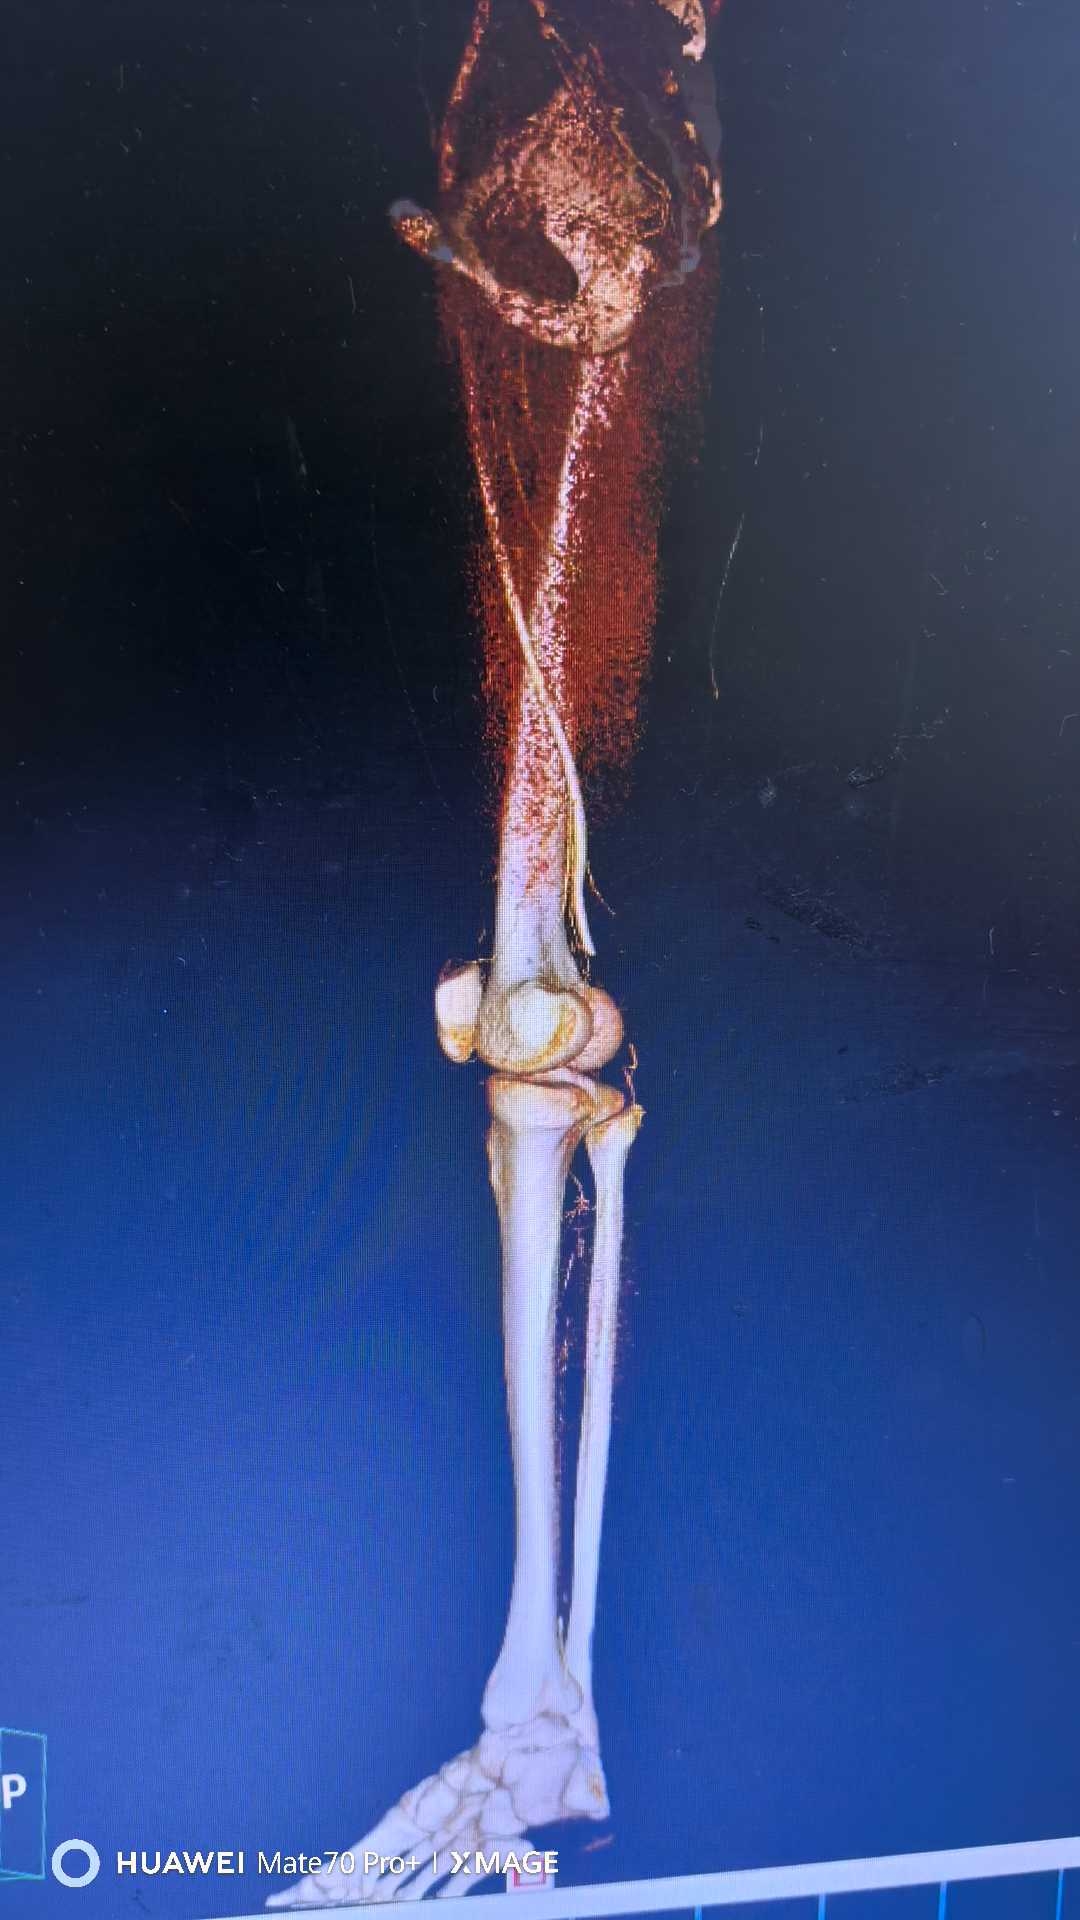

【检查】:

【临床诊断】:右下肢动脉闭塞(腘窝段)